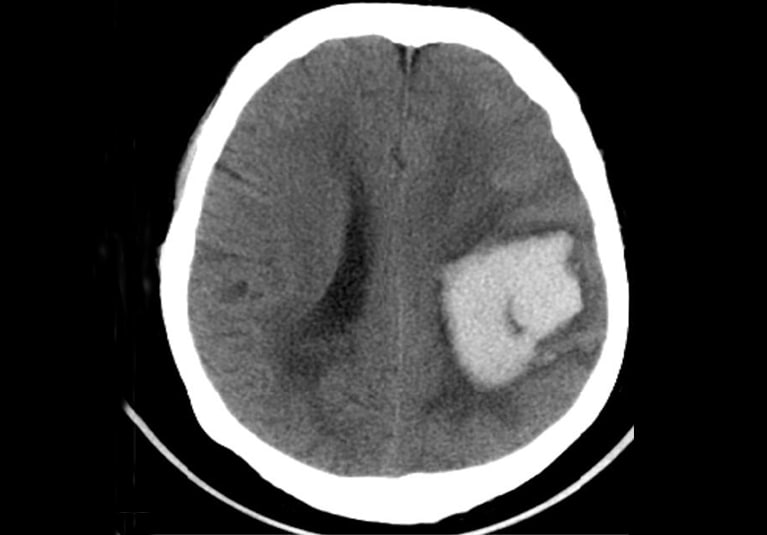

Using a head CT deep learning model to predict patient outcomes after moderate to severe traumatic brain injury

Researchers are examining whether deep learning analysis of computerized tomography (CT) results might yield information predicting long-term prognosis.